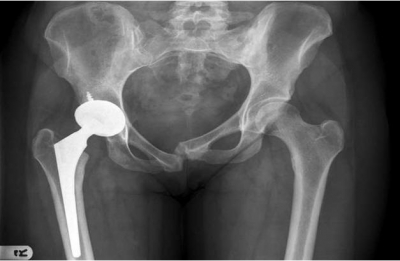

耻骨联合分离过大:会出现跨部增宽。耻骨联合分离过大,会出现跨部增宽。

耻骨联合处分离过大

耻骨移位:会出现长短腿以及影响步态(有很多产妇的步态足部的承重偏小指侧、大拇指没有推进、产后依然双脚足部过度外八)

耻骨变形:会有骨盆偏转,影响髋关节灵活度,出现骨盆旋转,导致腰椎变形,出现腰痛。

腰椎为中心,骨盆左右两边的宽度不等